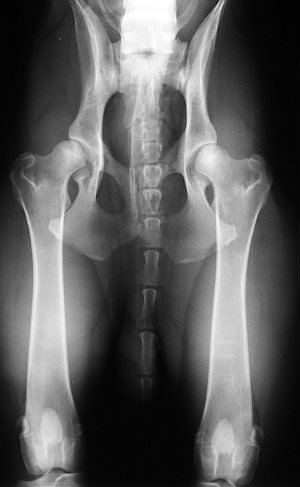

Bei der HD liegt eine Dysplasie vor - eine Fehlbildung also - dabei passen Kopf und Pfanne nicht richtig zueinander. Es kann sein, daß die Pfanne zu flach ausgebildet ist und infolgedessen der Kopf aus der Pfanne herausrutscht und an deren Enden scheuert.

Oft aber ist die Pfanne normal ausgebildet, jedoch der Kopf zeigt eine Mißbildung und scheuert in der normal geformten Pfanne.

Der Körper versucht eine "Reparatur" durch zusätzliche Knorpelbildung und später dann Knochenbildung. Dieser Vorgang ist als Arthrose bekannt.

Hunde werden mit normalen Hüftgelenken geboren und entwickeln im Alter von ca. 2 Monaten radiologisch nachweisbare Anzeichen einer „lockeren Hüfte“ . Eine Gelenkserkrankung entsteht meist im Alter zwischen 4–6 Monaten, oftmals auch erst später. Weiterhin verläuft der Schweregrad der HD linear zum Alter des Hundes. Obwohl HD sehr häufig vorkommt , zeigen die meisten betroffenen, insbesondere diejenigen mit milderen Formen der Hüftgelenksarthrose, wenn überhaupt, erst im hohen Lebensalter Lahmheitssymptome.